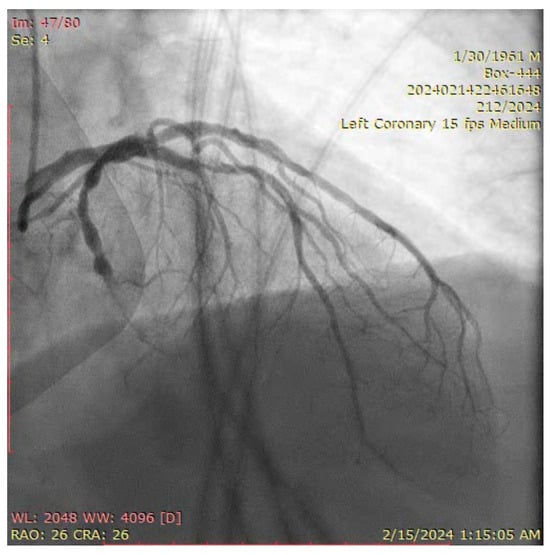

- Engage the left coronary artery with an EBU 4.0/8F guiding catheter. Wiring the three branches of the trifurcation (Floppy guide wires in LAD and RI, Hydrophilic guide wire in LCX) (Figure 14).